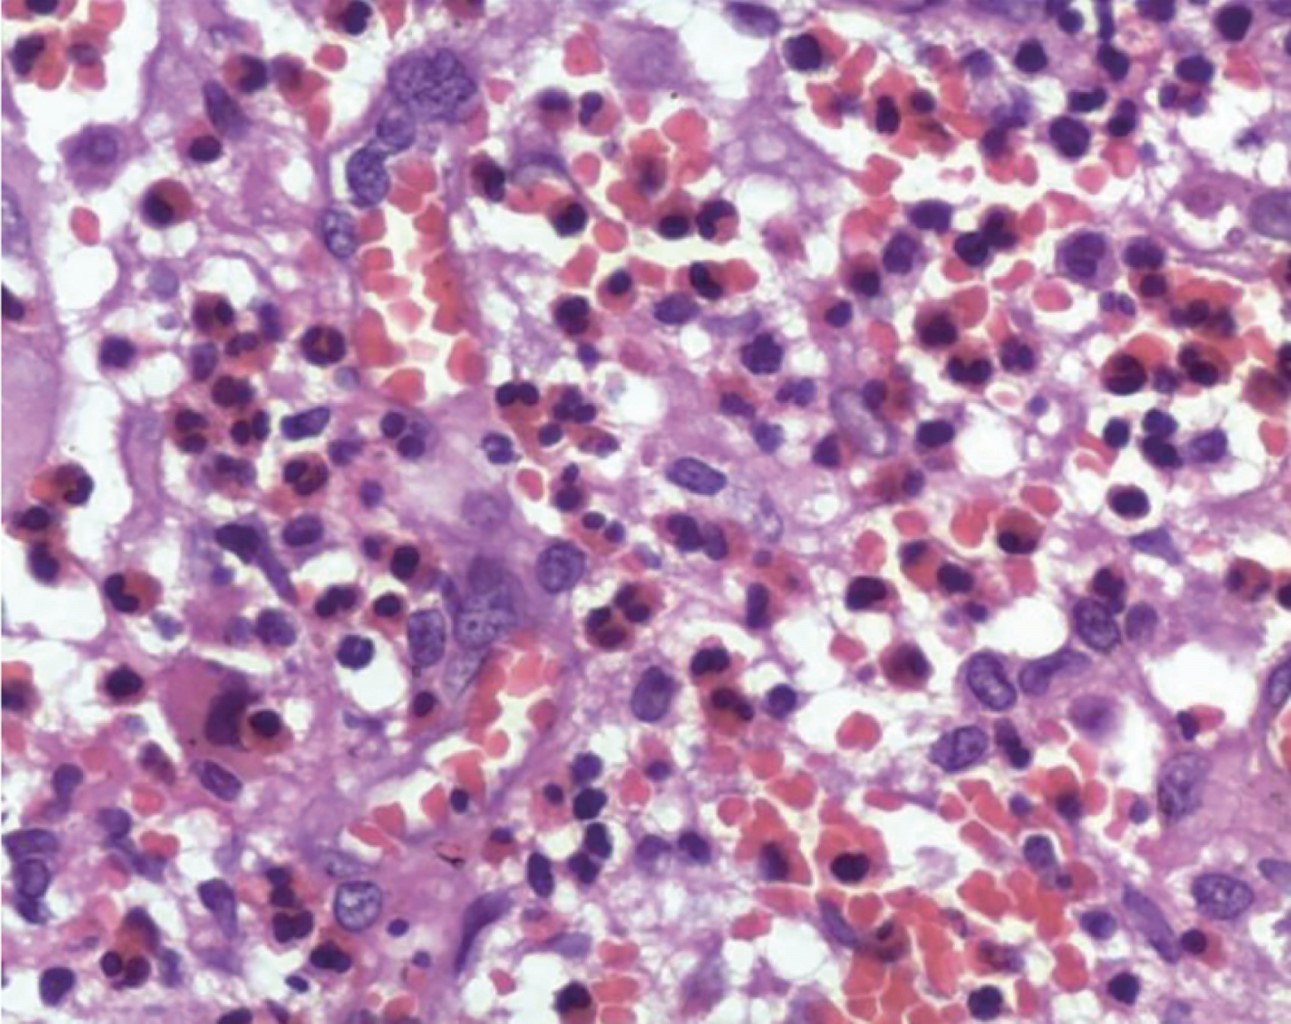

Informe histopatológico: 01/Junio/2023 el resultado indica que se identifican fragmentos de tejido fibroso laxo maduro bien vascularizado, el cual presenta áreas de hemorragia reciente y antigua, entre las que se aprecian mantos de células ovoidales y poligonales con amplio citoplasma eosinófilo, núcleos ovoidales con identaciones y pliegues centrales, entre las que se identifican numerosos eosinófilos y algunos grupos de células inflamatorias de tipo mixto.

Diagnóstico: los hallazgos son compatibles con histiocitosis de células de Langerhans.

Se confirma el estudio con el informe de inmunohistoquímica: con fecha 08/Junio/2023 en donde se obtienen resultados: S-100 positivo, CD1a positivo y Langerina positivo.

Se presenta microfotografías de cortes histopatológicos (Figuras 5, 6, 7 y 8).

Diagnóstico histopatológico. Microscopia óptica convencional: asociación de células inflamatorias con proliferación de células mononucleares grandes, redondas a ovaladas, con forma epitelioide, citoplasma eosinófilo y núcleo ranurado que recuerda a los granos de café en apariencia o riñón. Células dendríticas inmaduras sin extensiones dendríticas, que han sufrido la pérdida o una reducción significativa de algunas funciones de la célula de Langerhans normal. Producen una serie de citoquinas (interleucinas, factor de necrosis tumoral alfa [TNF-α] y factor estimulante de colonias de granulocitos y macrófagos [GM-CSF]). También se han descrito algunas mitosis y apoptosis atípicas, detectándose necrosis en casos con alta tasa de proliferación. La necrosis puede imitar otras condiciones infecciosas y neoplásicas como la tuberculosis y la enfermedad de linfoma de Hodgkin.3,18